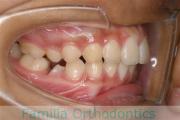

出っ歯を治したいということで小学生の時に来院されました。中学生になるまで経過観察をして、診断、上下左右から小臼歯を抜歯してマルチブラケット法にて治療を行いました。2年強、30回程度の通院が必要でした。

口元の突出感も大きく改善しています。

上下とも前歯の叢生(でこぼこ、凹凸、ガタガタ)がありましたので、保定をしっかりやらないと後戻りのリスクが出てきます。